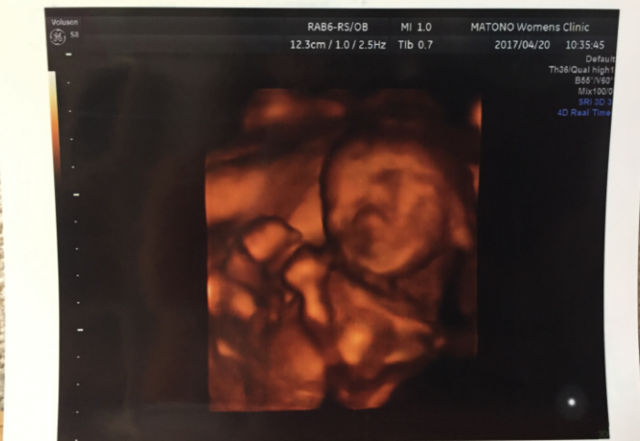

20週5日(20w5d・男の子)|あぁこ さん(31歳)

エコー写真撮影時のエピソード:

このエコー写真は検診に行き始めてから初めての立体的な写真です。この時点で男の子というのは確定だったのですが、顔立ちがしっかりしていて男前だなと思ってしまいました。(とても親バカ(笑)です)

エコーではいろんな角度から見せてもらえたりしてすごいなぁ…と感心しまくりでした。仕事もしていたので日に日に大きくなる我が子に喜びを感じている反面お腹が重たく体力的にもしんどかった記憶があります。

早産の危険もありましたが無事に産まれて来てくれて顔を見た時はエコー写真の面影があったので笑ってしまいました(*´-`)